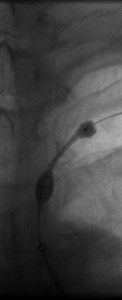

The 4 images you see above were recorded by me during primary stenting of irregular atherosclerotic stenosis of the left subclavian artery in a 54-year-old Hispanic female who was referred to my interventional radiology clinic for management of the stenosis. She had presented to her primary care physician with symptoms of hindbrain ischemia upon using her left upper limb and earlier workup confirmed left subclavian arterial stenosis. The 2 top images illustrate the character and severity of her disease, the first image in the bottom row shows the process of balloon-expandable stenting of the disease, while the 2nd image in the bottom row reveals complete elimination of the stenosis and reappearance of the left vertebral and internal mammary arteries, which were invisible on the pre-intervention angiograms reflecting the severity of the stenosis.